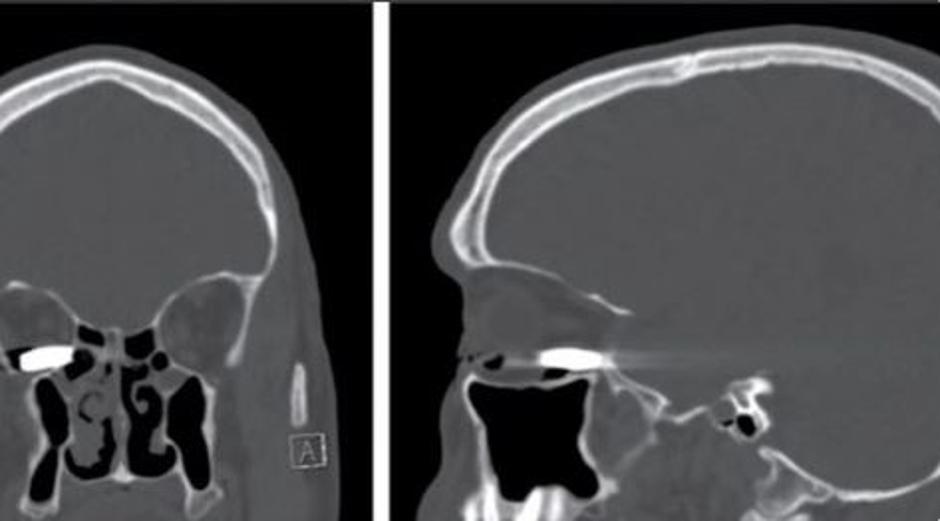

42-letnika so ustrelili iz pištole kalibra 22mm. Krogla je prebila lesena vrata in se ustavila v njegovi očesni votlini, ob tem pa ni poškodovala nobenega dela lobanje, kar jih je zelo presenetilo. Moškega so operirali, odstranili metek, bolnik pa je povedal, da sploh ni občutil bolečine in da je še vedno odlično videl.